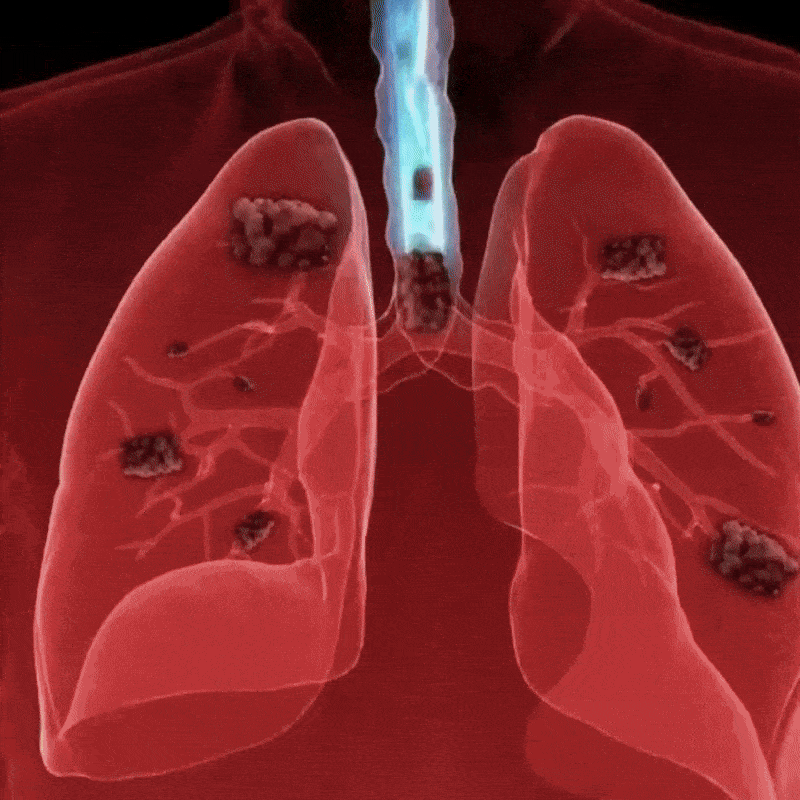

Was sie fanden: In den Atemwegen jedes einzelnen Patienten befand sich eine dichte Schleimschicht ganz unten – unter dem frischen Schleim, unter der Reichweite jeder Behandlung.

Die Schicht war seit Monaten dort gewesen. Manchmal über ein Jahr.

Die Flimmerhärchen – diese winzigen Härchen, die den Schleim hinaustransportieren – waren vollständig darunter begraben. Funktionslos.

Die molekulare Struktur war anders. Dichter.

„Aber darunter gibt es eine weitere Schicht. Alter Schleim. Monate alt, vielleicht Jahre. Ihre Flimmerhärchen sind darunter begraben."

„Wenn Sie sich hinlegen, verschiebt die Schwerkraft ihn nach oben. Blockiert Ihre Atemwege. Deshalb wachen Sie würgend auf. Deshalb hat nichts funktioniert, was Sie versucht haben."